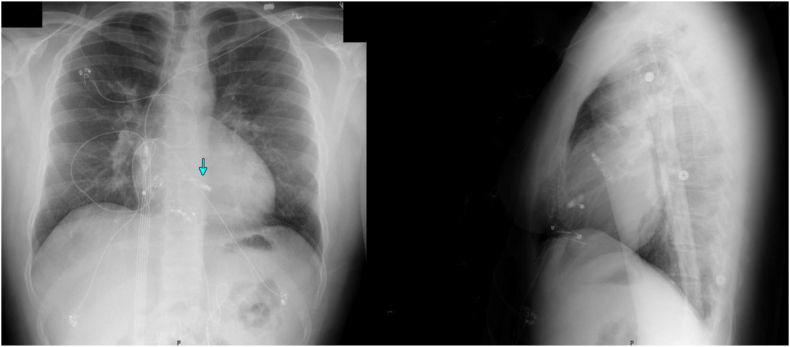

Removal of previous pacemaker leads via mechanical extraction occurred and implantation of Aveir DR leadless pacemaker was performed under anesthesia via right femoral vein access without complication. Follow-up demonstrated Aveir VR threshold of [email protected] ms, R-wave of 8.9mV, impedance of 490Ω, and the Aveir AR threshold of [email protected] ms, P-wave of 3.7mV, and impedance of 400Ω.

This case demonstrates safety and efficacy of dual chamber leadless pacemaker implantation in an ACHD patient.